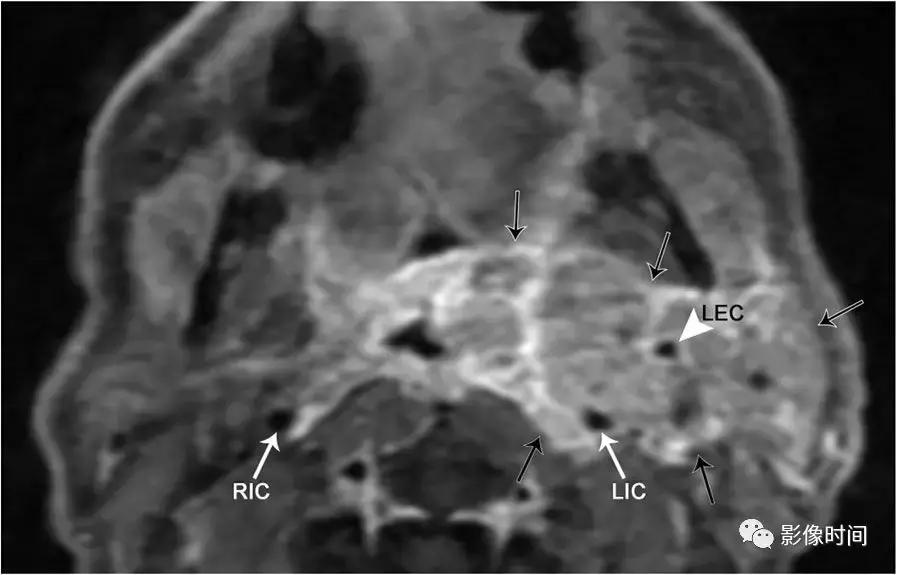

10.淋巴瘤:霍奇金淋巴瘤和非霍奇金淋巴瘤常累及头颈部,影像检查无法将两者区分开。非霍奇金淋巴瘤多见,80-85% 为弥漫大 B 细胞淋巴瘤。患者一般出现无痛性头颈部肿块,伴发烧,体重减轻,盗汗要想到淋巴瘤的可能性。CT 或 MRI 上,淋巴瘤可以单发或多发,多发病灶可见相互融合,常常推挤或包饶周围结构,增强扫描呈不同程度的强化,重要一点:淋巴瘤包饶血管,但不会导致血管管腔狭窄,这种特征有助于和其他疾病区分。虽然 CT 是淋巴瘤初步评估和分期的主要标准,但它只提供结构信息,正电子发射断层显像 (PET) 在淋巴瘤中的作用越来越大,因为可以反映其功能。PET 是评估淋巴瘤治疗的反应以及在治疗后发现残余或复发的关键。

轴位 T1WI+C 显示不均匀强化肿块,完全包裹左侧颈内 (LIC) 和颈外动脉 (LEC)。注意左侧颈内动脉的管腔与右侧颈内动脉 (RIC) 的管径一致。